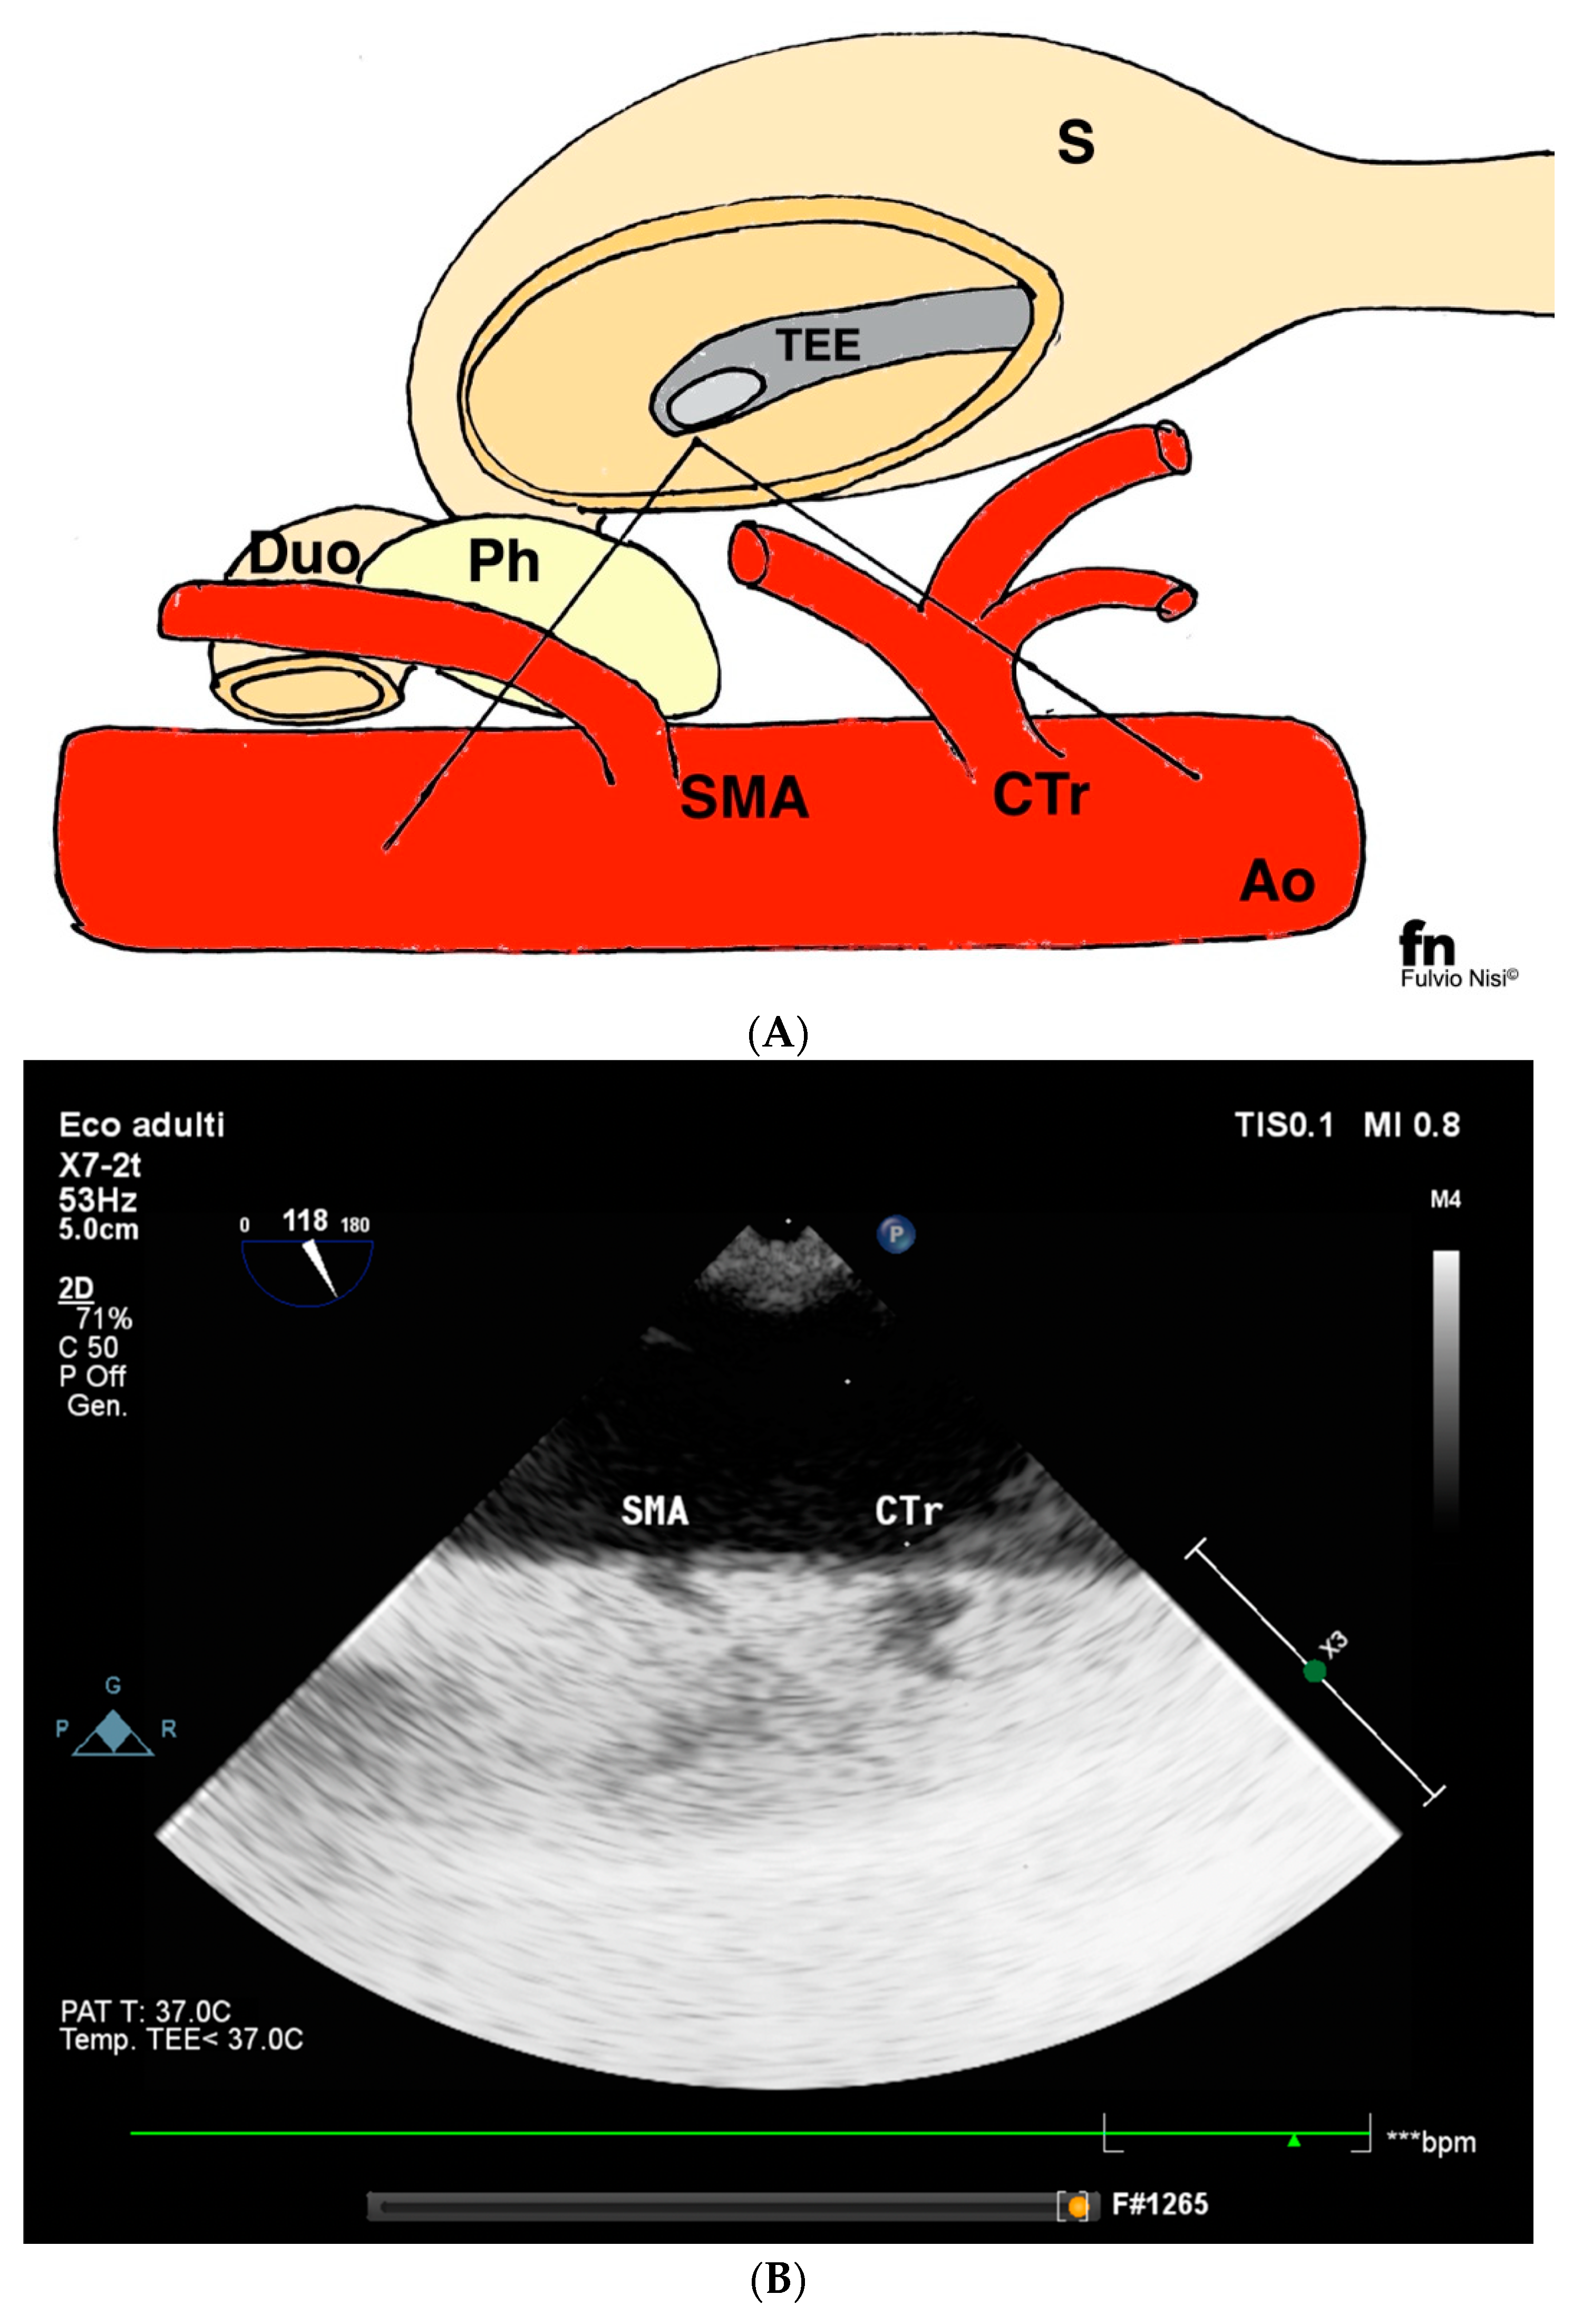

2.1. Technique Description